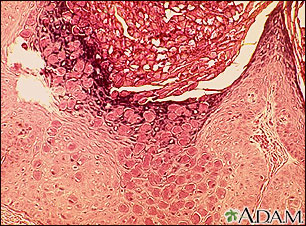

Molusco,aspecto microscópico

Este es el aspecto al microscopio de una lesión del molusco contagioso, perteneciente a la familia de los poxvirus. A la vista, estas lesiones son pequeñas, elevadas y perladas.